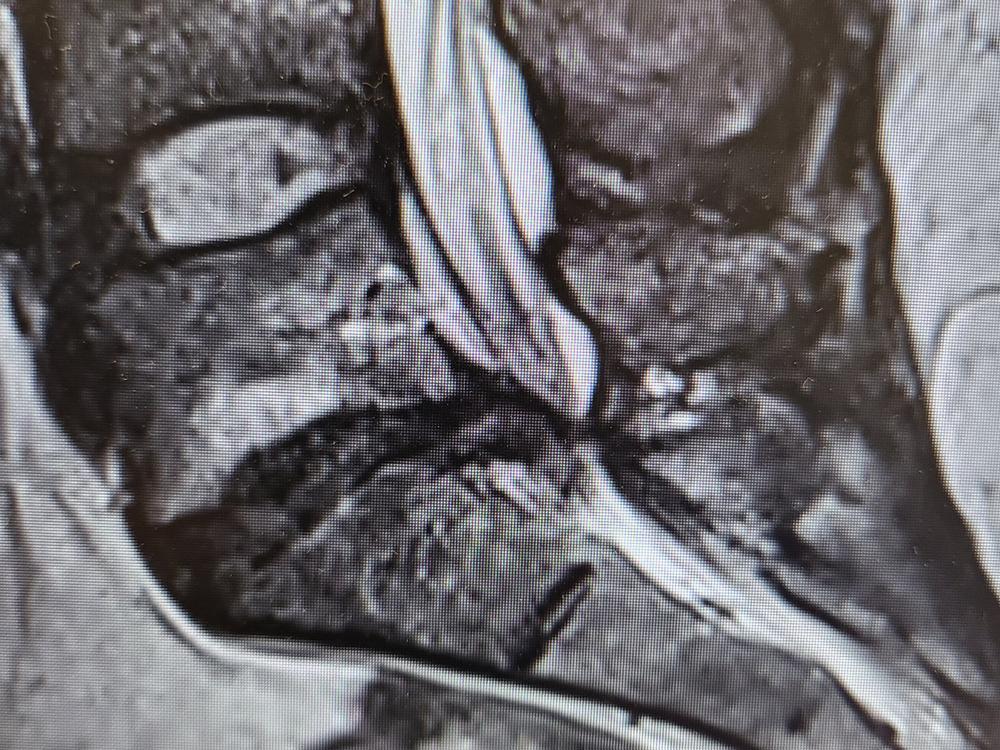

Lucy is a young hairdresser who is passionate and really loves what she does. In 2021 she had a accident in her salon that resulted in crushing her lower L5/S1 disks. After 9 months she had surgery to remove fragments of disk that was compressing her s1 and s2 nerves majorly. Sadly the remaining disk fragments had blown out in to her spinal cord again after 2 weeks post op. She has recently received a spinal fusion ( alter body L4/S1 inter spinal fusion disk replacement). Sadly due to the severity of her injury she is unable to work full time and had to close her business resulting in debts. Any donations will be greatly appreciated to help her with medical expenses and clear her business debts.

So it has been 12 weeks since alter body spinal fusion of my L4/S1. So far the pains and sciatica have not gone away at all. Have had a xray that shows the replacement disks sitting in the correct area but has not started fusion process yet.